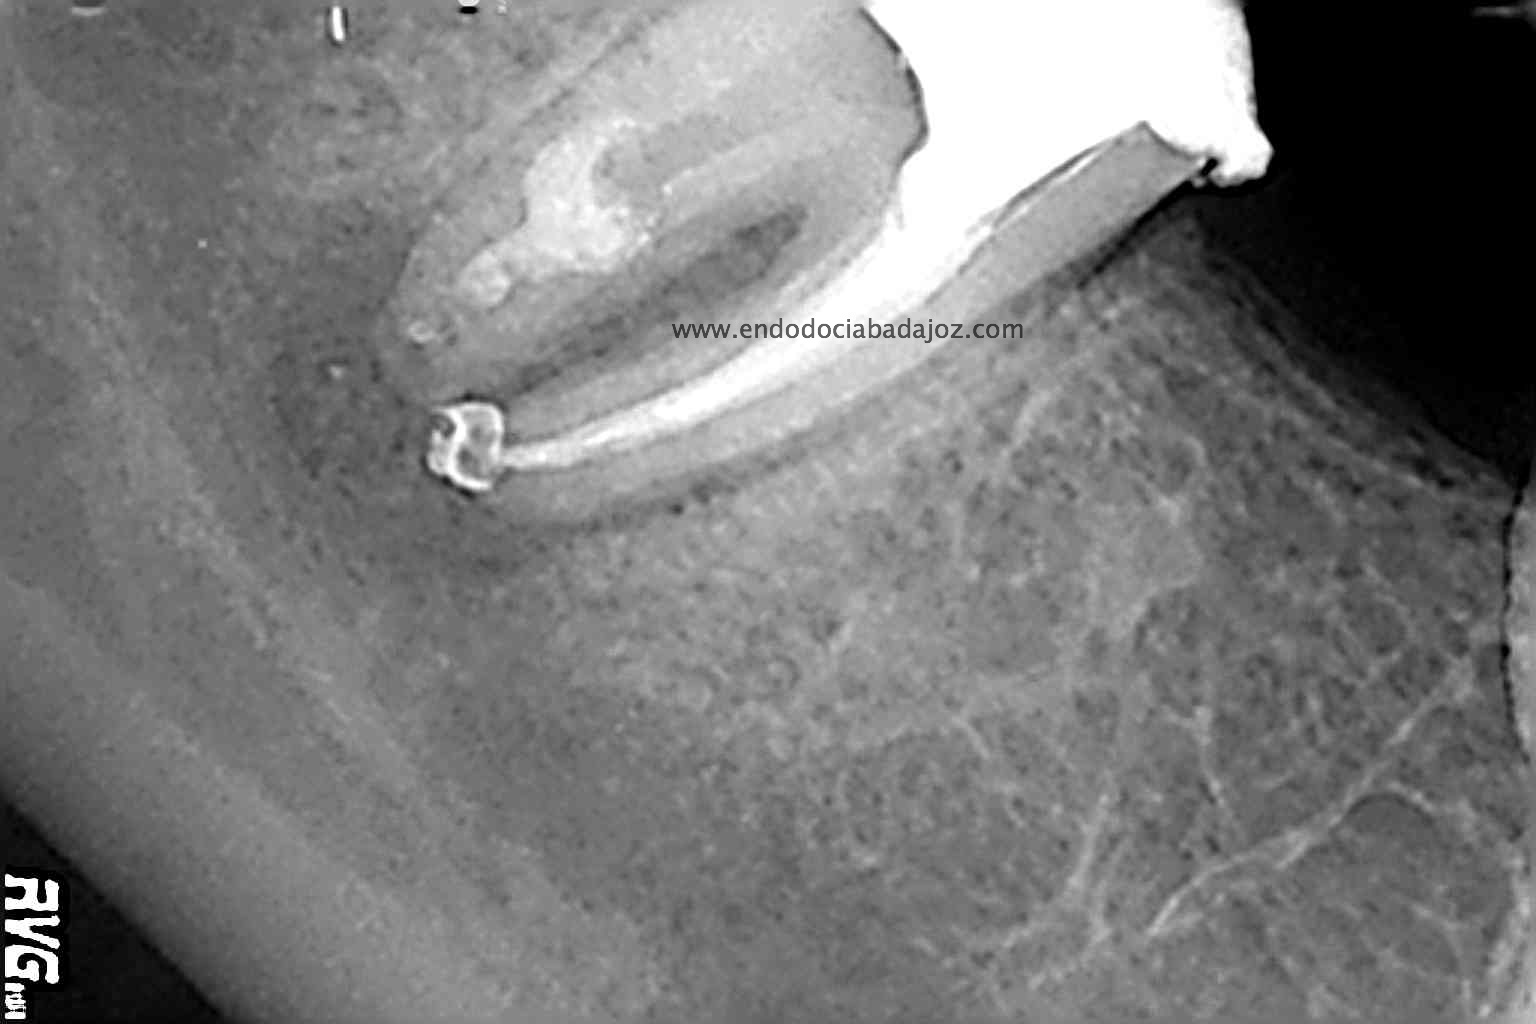

Acude a nuestra clínica una paciente que llamamos a revisión después de realizarle un retratamiento endodóntico de la pieza 4.7 hace unos meses. Si recordamos el día que llegó, no se nos presentaba muy bien el caso, y como otros muchos casos, intentamos retratarlo, pues pensamos que podríamos manejarlo.

En un primer paso, retiraríamos el perno y los vástagos del Thermafil, un sistema del que no soy muy partidario, aunque en algunos casos resulta beneficioso.

Con ayuda del microscopio, pudimos confirmar que se trataba de una reabsorción interna en el tercio medio y una reabsorción radicular del conducto distal.